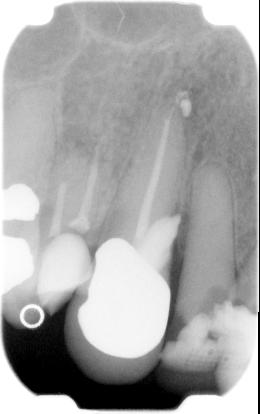

ad e. Een apicale perforatie ontstaat als een ledge is gemaakt waardoor er lengte is verloren. De behandelaar wil toch weer op lengte komen en vijlt met te dikke stugge niet voorgebogen vijlen door, totdat het opeens weer gemakkelijk gaat om op lengte te komen. Dan is vermoedelijk een apicale perforatie gemaakt. Meten met de elektronische lengtebepaler en vervolgens een lengtefoto maken. De plek waar de vijlpunt uitkomt geeft een aardige indicatie of het een perforatie is of dat toch het gewone kanaal weer doorgankelijk is gemaakt.

De perforatie kan gesloten worden door een gewone kanaalvulling te plaatsen, of door het aanbrengen van MTA (Pro Root) als handpluggers

ongeveer ter plaatse kunnen komen.

Als een perforatie in een krom kanaal een aantal millimeters vanaf de apex heeft plaats gevonden, is het verstandig om het apicale kanaalgedeelte en de perforatie beide af te sluiten met MTA (Pro Root).